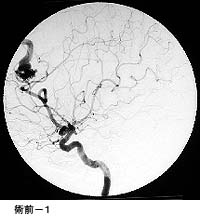

脳動静脈奇形に対する液体塞栓物質を用いた治療

治療により異常血管は閉塞されました。